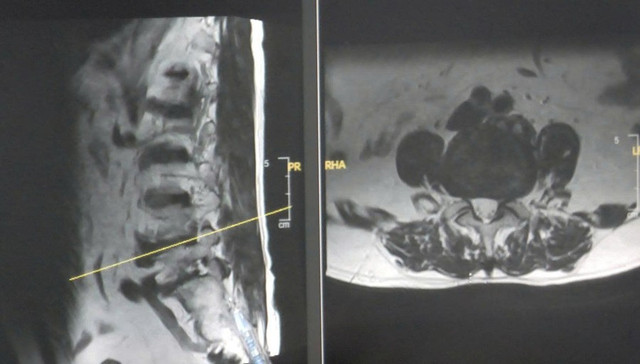

Qua kiểm tra lâm sàng và chụp cộng hưởng từ (MRI) tại bệnh viện, các bác sĩ phát hiện ông L. bị thoát vị đĩa đệm cột sống thắt lưng L4–L5. Khối thoát vị đã tách rời, chèn ép mạnh vào rễ thần kinh tại vị trí ngoài lỗ liên hợp.